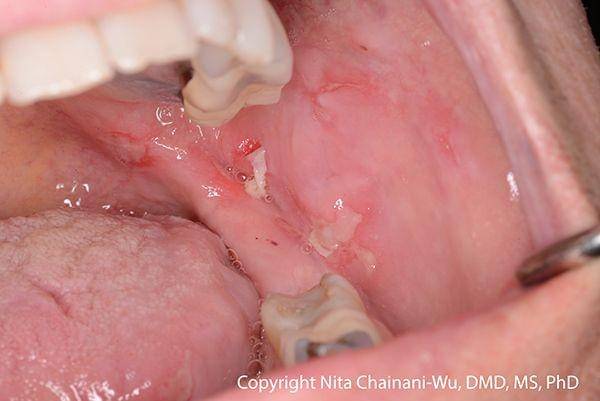

Luka mulut yang menyakitkan sering terjadi pada orang dengan pemfigus vulgaris. Sekitar 50–70 persen penderita pemfigus vulgaris mengalami luka di mulut sebelum lepuh muncul di kulit.

Luka mulut dimulai sebagai lepuh, yang dengan cepat pecah menyebabkan luka yang menyakitkan.

Luka ini bisa sangat menyakitkan sehingga beberapa orang berhenti makan makanan padat dan menggunakan sedotan untuk minum. Jika luka berkembang di tenggorokan, berbicara bisa terasa menyakitkan.